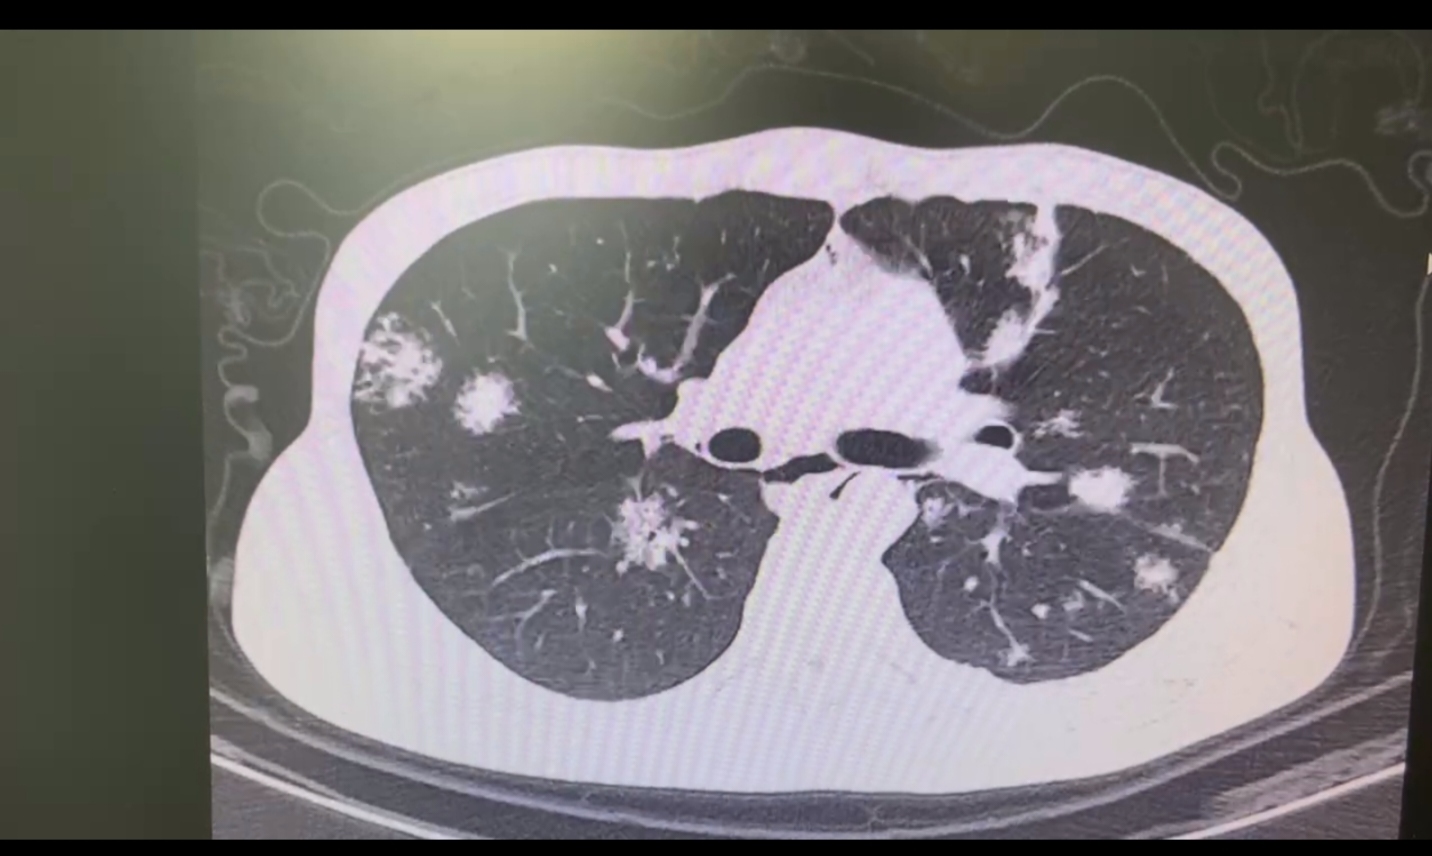

再看看惡性肺結節,這可就像是那些有背景的大妖怪了,可能存在遺傳傾向。

有些人天生就攜帶一些像“BRCA1和BRCA2”這樣的“神秘法寶”(易感基因),這就增加了他們患上肺部結節的風險。就像有些家族性肺癌患者,他們就像是妖怪家族里有特殊本領的成員,攜帶的基因突變會提高患上肺癌(包括肺部結節)的風險。

部分惡性肺結節(如早期肺癌表現)可能和遺傳因素有關。

某些家族中存在特定的基因突變(如EGFR、BRCA等基因異常),就像是妖怪家族有獨特的“魔力傳承”,這些基因變異增加了患肺癌的風險,讓肺部較早出現結節。不過,這可不是直接遺傳肺結節本身,而是遺傳了對肺癌的易感性,使得家族成員在相同環境因素作用下,患肺結節及肺癌的概率相對較高,就像妖怪家族的后代更容易走上“作惡”之路。